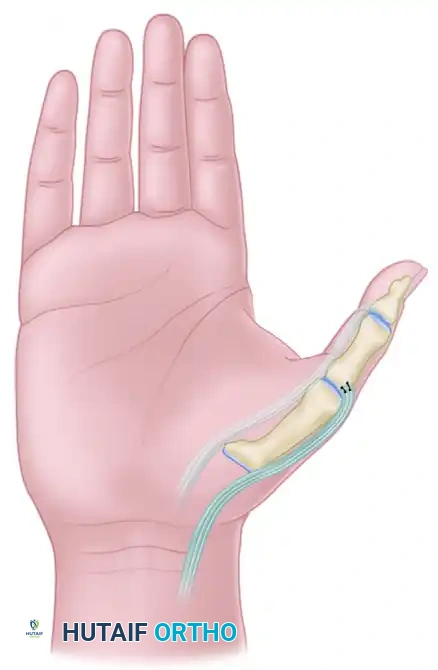

REDIRECTION OF EXTENSOR POLLICIS LONGUS (MANSKE TECHNIQUE)

While the Smith procedure addresses the volar deforming forces, the Manske technique focuses on optimizing the dorsal extensor mechanics. In the normal hand, the EPL tendon (residing in the third dorsal compartment) acts as an adductor and extensor of the thumb. In the spastic hand, this adduction vector exacerbates the thumb-in-palm deformity.

By surgically releasing the EPL from the third compartment and redirecting it through the first dorsal compartment, its vector is shifted radially. The EPL is transformed from an adductor-extensor into a pure abductor-extensor, providing a powerful dynamic force to pull the thumb out of the palm.

5. Rerouting the EPL Tendon

- Preparation of the Pulley: The first extensor retinacular compartment (housing the APL and EPB) will serve as the new anatomical pulley for the EPL.

- Passage: Pass a curved hemostat or a specialized tendon passer from the dorsal incision on the thumb, routing it proximally along the anatomical course of the extensor pollicis brevis (EPB) tendon.

- Through the Compartment: Direct the instrument through the first extensor compartment until it emerges at the distal radius incision.

- Redirection: Grasp the free end of the EPL tendon with the hemostat. Retract the instrument distally, pulling the EPL tendon through the first extensor compartment and out into the dorsal thumb wound.